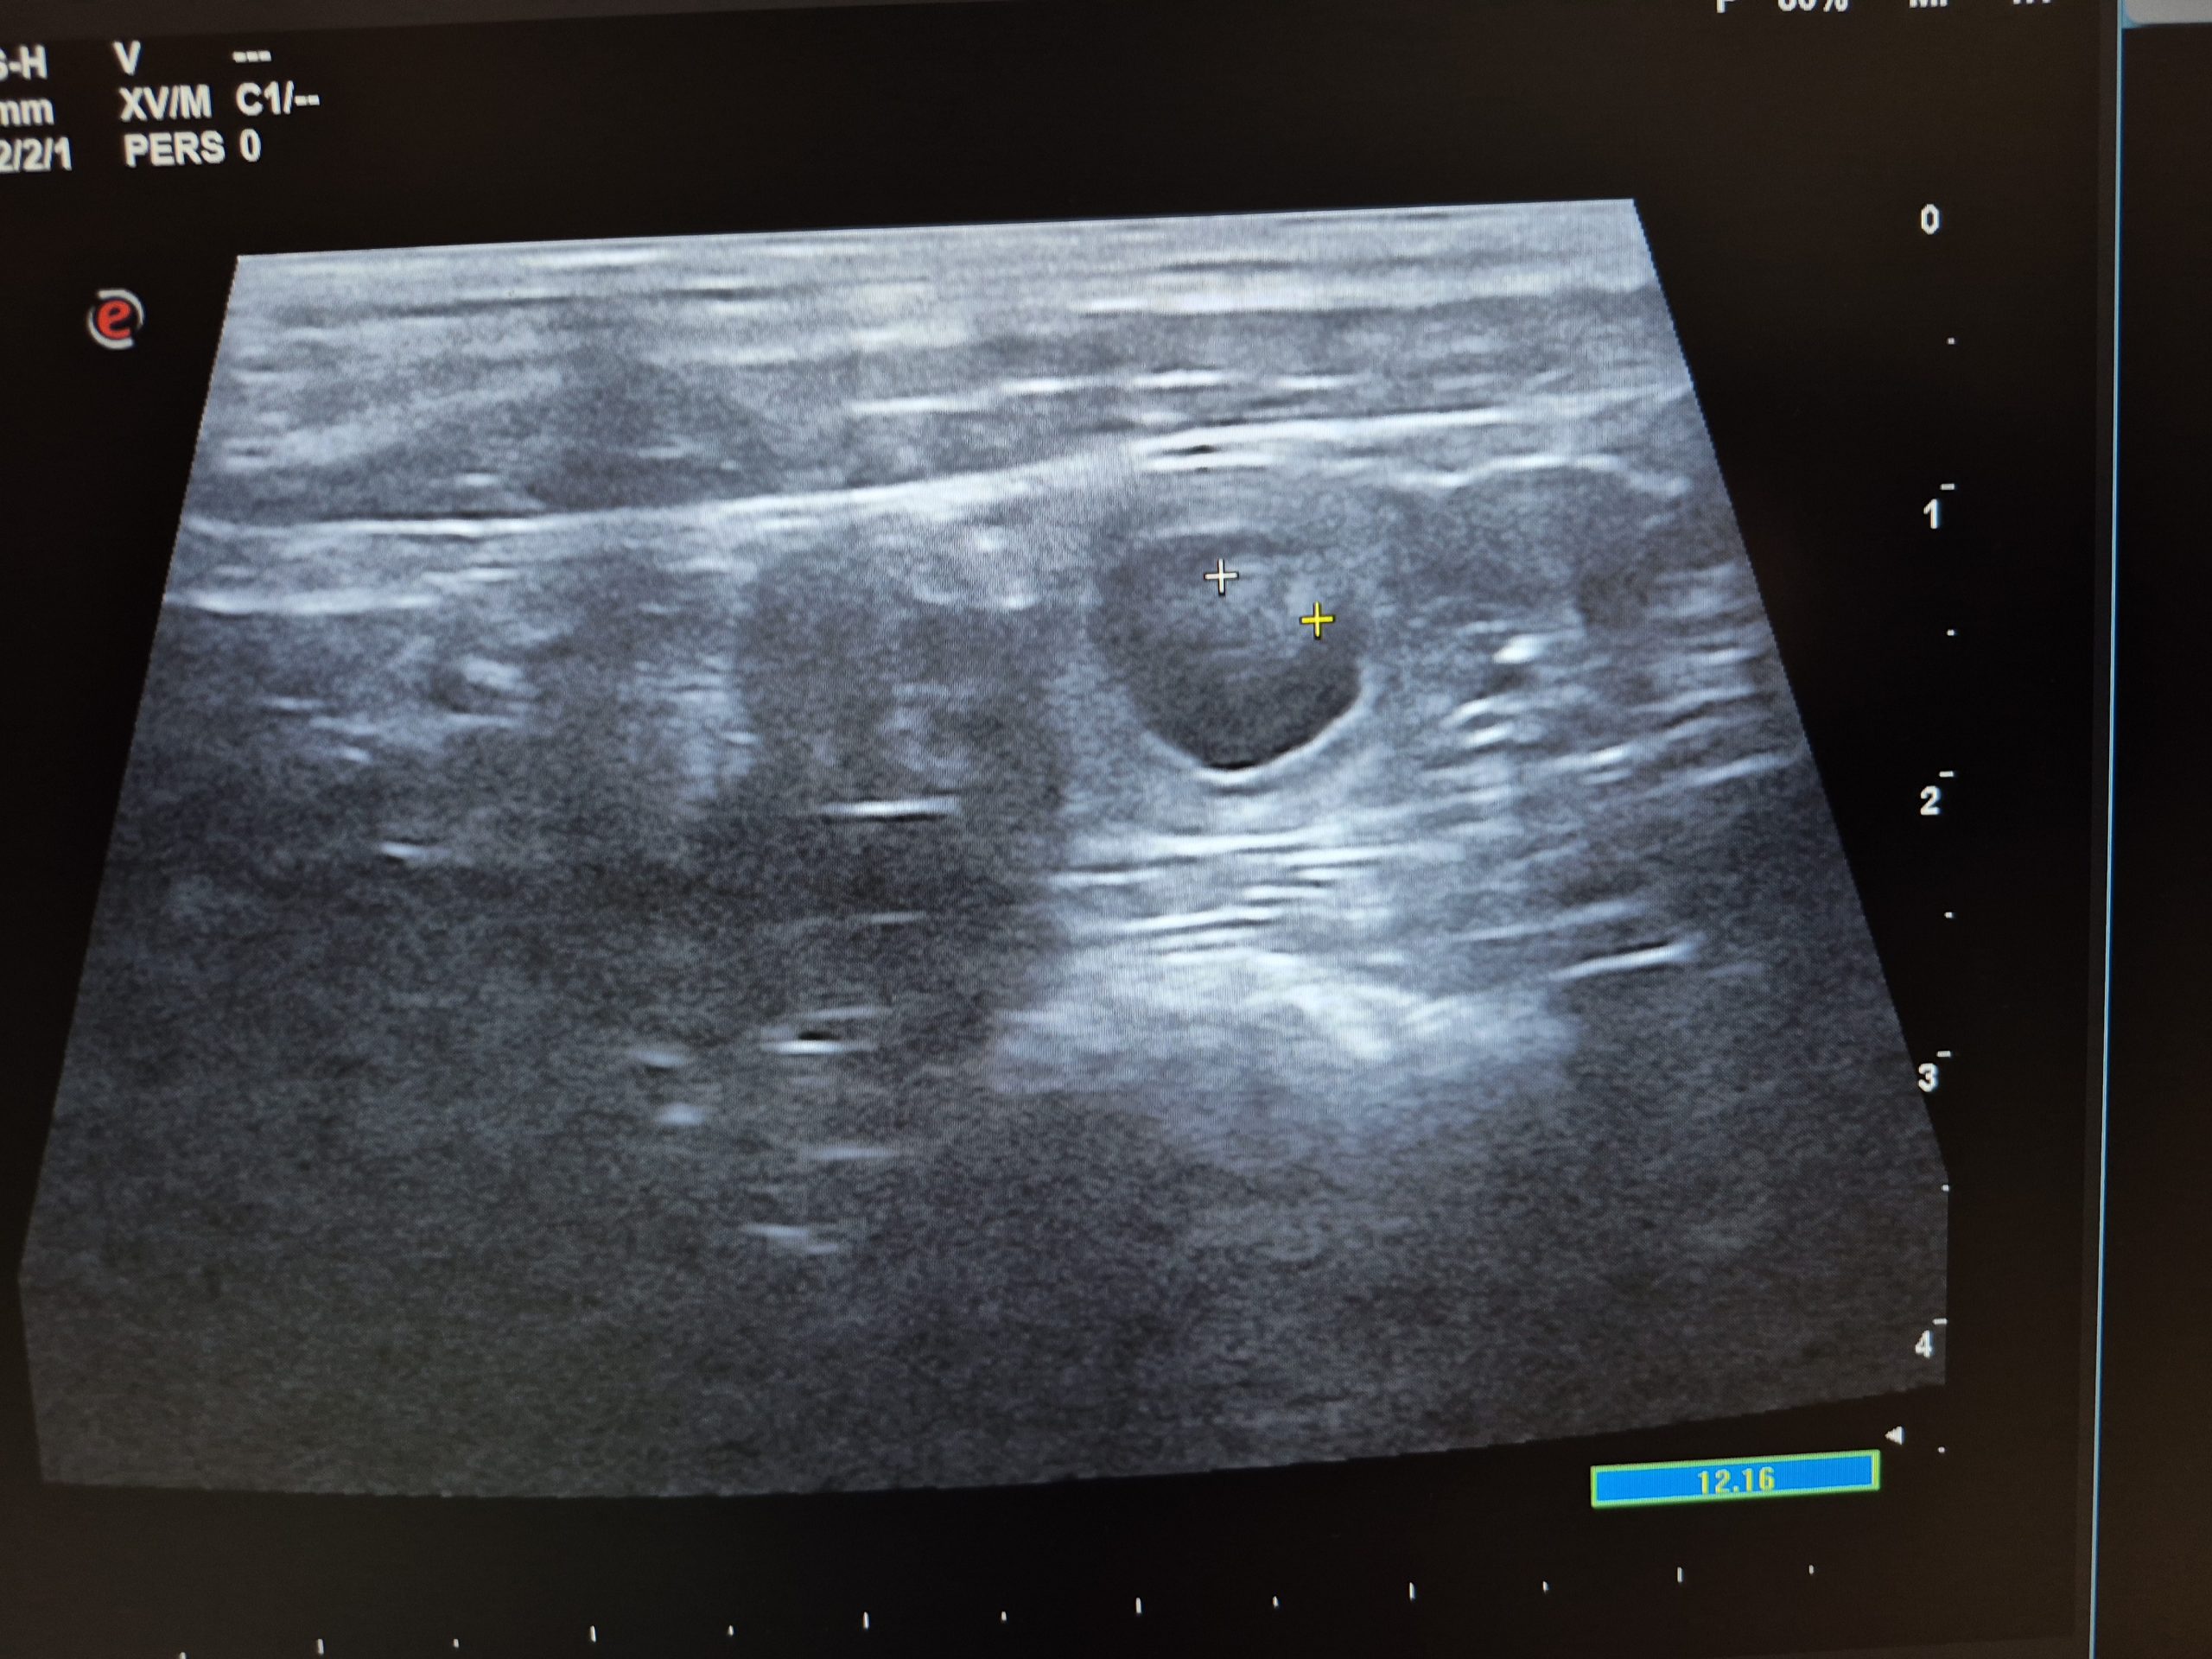

Update 31.07.2025: Wir waren beim Ultraschall und Namaari ist tragend!